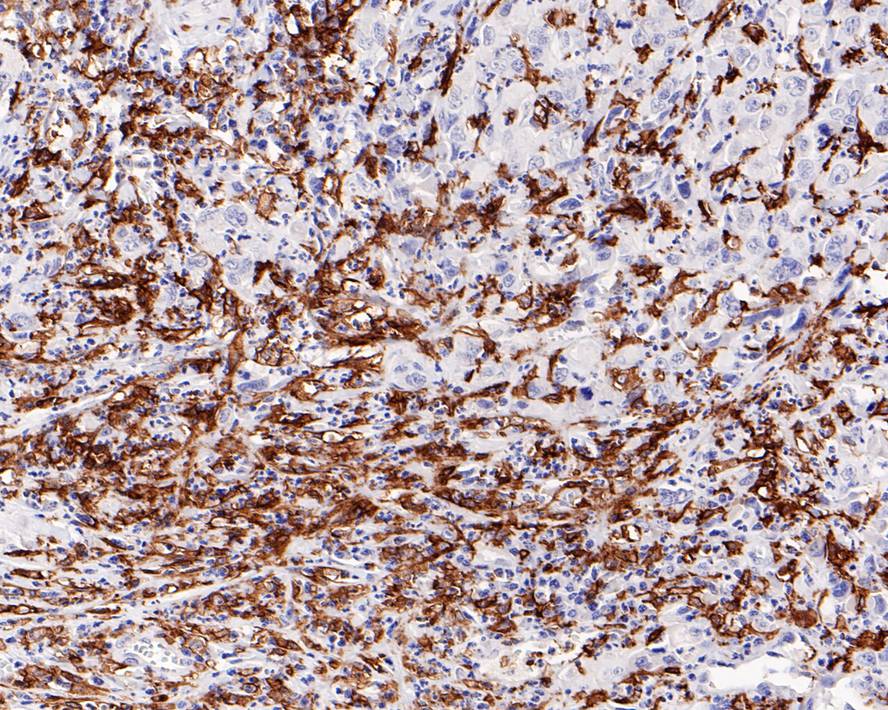

CD16 Recombinant Rabbit Monoclonal Antibody [PD00-12]

IHC-P